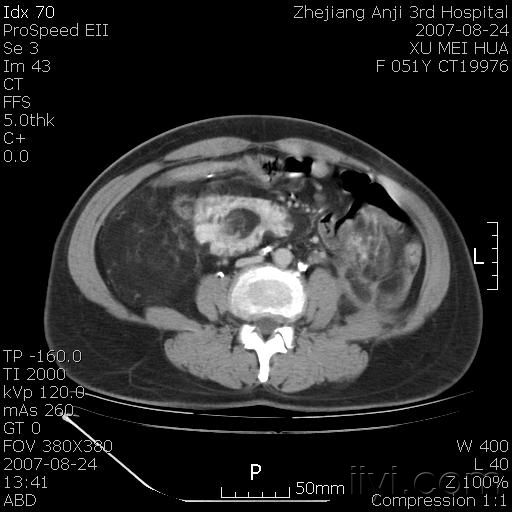

以下是引用还珠格格在2007-8-27 10:19:00的发言:[br]双侧肾脏形态失常,可见巨大的以低密度脂肪为主的混合性肿块,占据中下腹,残留的肾组织轻度强化,增强后肿块内实质部分呈峰窝状强化,低密度区无强化。另左侧肾盂轻度积水。根据病史 考虑 双肾血管平滑肌脂肪瘤可能性大。[br] 鉴别诊断 1、脂肪瘤,境界清楚,肿块内完全是脂肪,几乎没有软组织成分; 2、畸胎瘤:罕见,除有软组织成分外,另一特征是有钙化或骨化影组织。